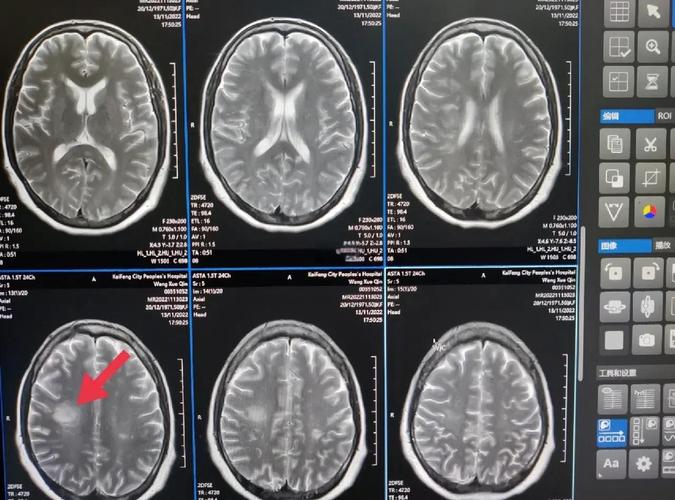

(图片来源网络,侵删)

CT只是一个初步的筛查工具,医生会结合您的具体情况,制定下一步的诊疗计划。

- 头颅MRI(磁共振成像): 这是诊断脑梗最精确的检查,它比CT更敏感,能更早、更清晰地发现小的梗塞灶,还能区分是新发的还是陈旧的。